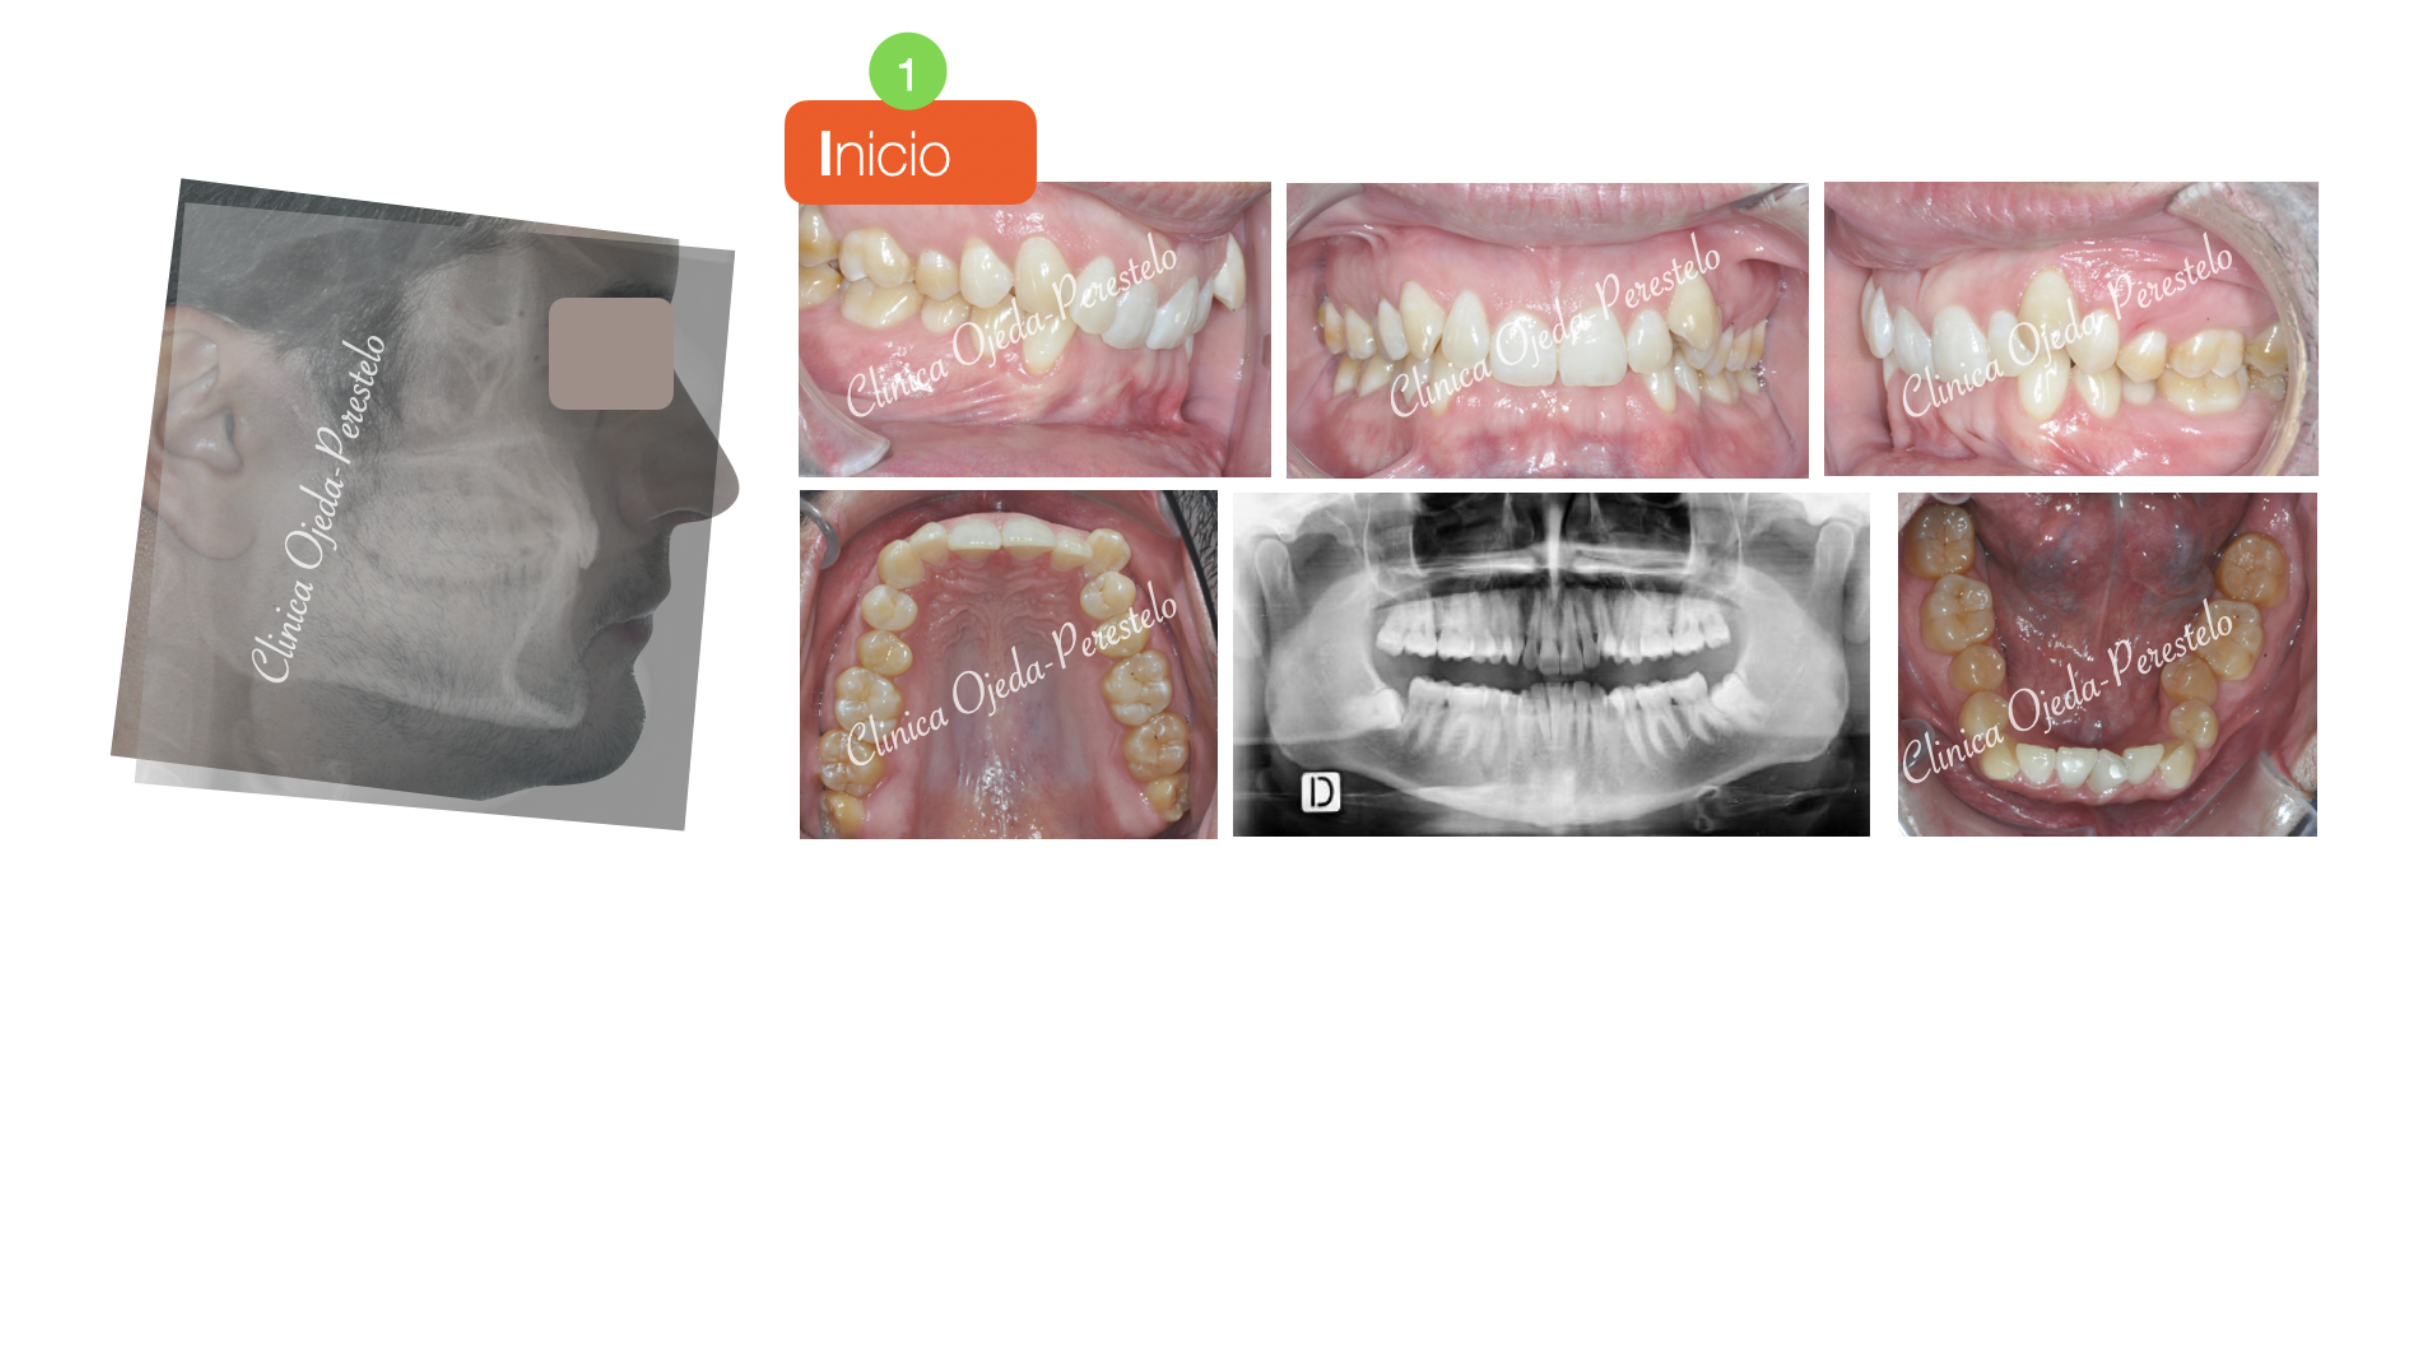

Clase II con apiñamiento y sobremordida severa

Presentamos este caso con apiñamiento severo y sobremordida muy aumentada  tratado con alineadores y con extracción de los cordales superiores.

Durante el tratamiento  hemos aprovechado el espacio de los cordales para  distalizar con MT los molares además de expandir, alinear y nivelar la arcada superior. En la arcada mandibular se ha realizado una expansión y algo de  stripping a efectos de poder “ordenar” las piezas, combinando alineadores con elásticos intermaxilares.